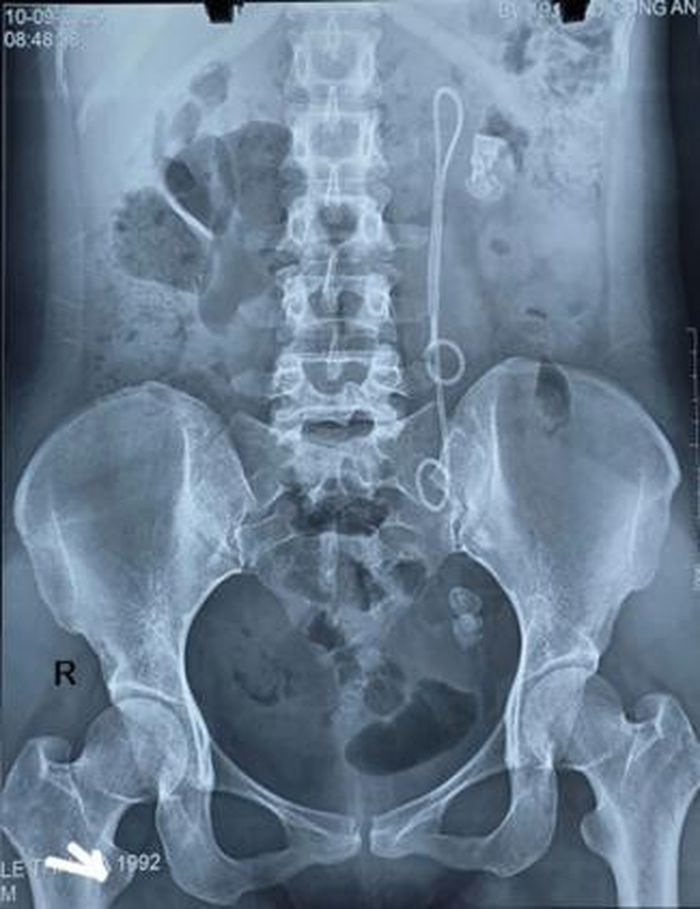

Qua thăm khám lâm sàng và cận lâm sàng, bệnh nhân được chẩn đoán sỏi thận trái và sỏi niệu quản trái đoạn 1/3 dưới. Đặc biệt, bệnh nhân còn Sonde JJ (một thiết bị y tế) đặt 15 năm chưa rút.

Trường hợp này, do Sonde JJ tồn tại tới 15 năm, bệnh nhân xuất hiện sỏi to ở nhiều vị trí, Sonde bám sỏi và di chuyển bất thường, khiến quá trình điều trị phức tạp, tiềm ẩn nhiều nguy cơ.

Hình ảnh XQ của bệnh nhân. Ảnh: Bệnh viện 19-8